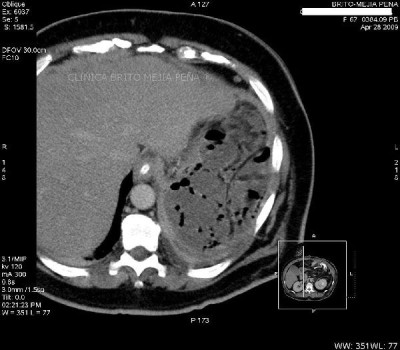

Absceso sub diafragmático axial